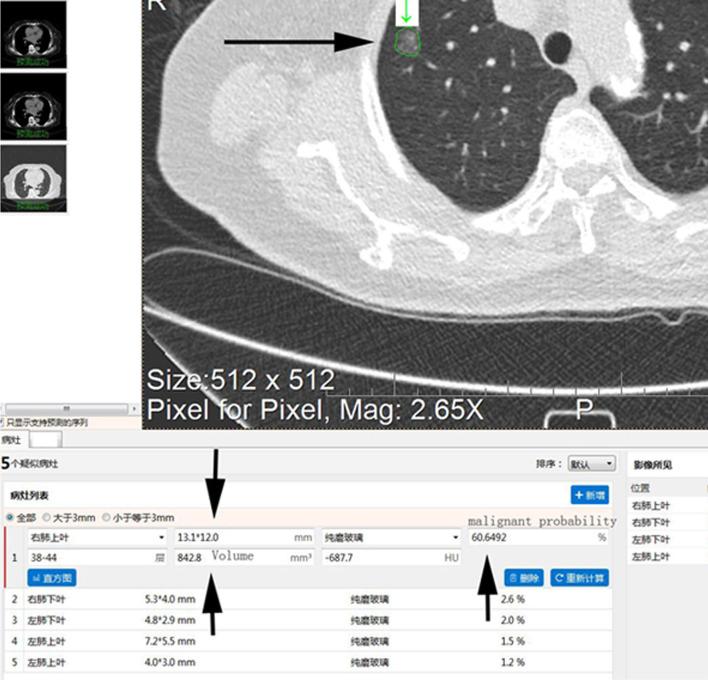

A total of 113 patients with pulmonary nodules were screened using LDCT. For nodules with the largest diameters, an HRCT local-target scanning program (combined scanning scheme) and a conventional-dose CT scanning scheme were also performed. Lung nodules were subjectively assessed for image signs and compared by size and malignancy rate measured by AI-assisted software. The nodules were divided into improved visibility and identical visibility groups based on differences in the number of signs identified through the two schemes.

The nodule volume and malignancy probability for subsolid nodules significantly differed between the improved and identical visibility groups. For the combined scanning protocol, we observed significant between-group differences in subsolid nodule malignancy rates.

使用LDCT对113例肺结节患者进行筛查。对于最大直径的结节,还执行了HRCT局部靶扫描程序(联合扫描方案)和常规剂量CT扫描方案。对肺结节的图像征象进行主观评估,并通过AI辅助软件测量的大小和恶性率进行比较。根据两种方案识别出的征象数量差异,将结节分为可见性改善组和可见性相同组。

实性结节的结节体积和恶性概率在可见性改善组和可见性相同组之间存在显著差异。对于联合扫描方案,我们观察到实性结节恶性率在组间存在显著差异。